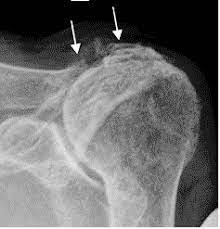

- Desplazamiento: Cadera - axialmente y Hombro - cranealmente

- Erosiones en áreas desnudas